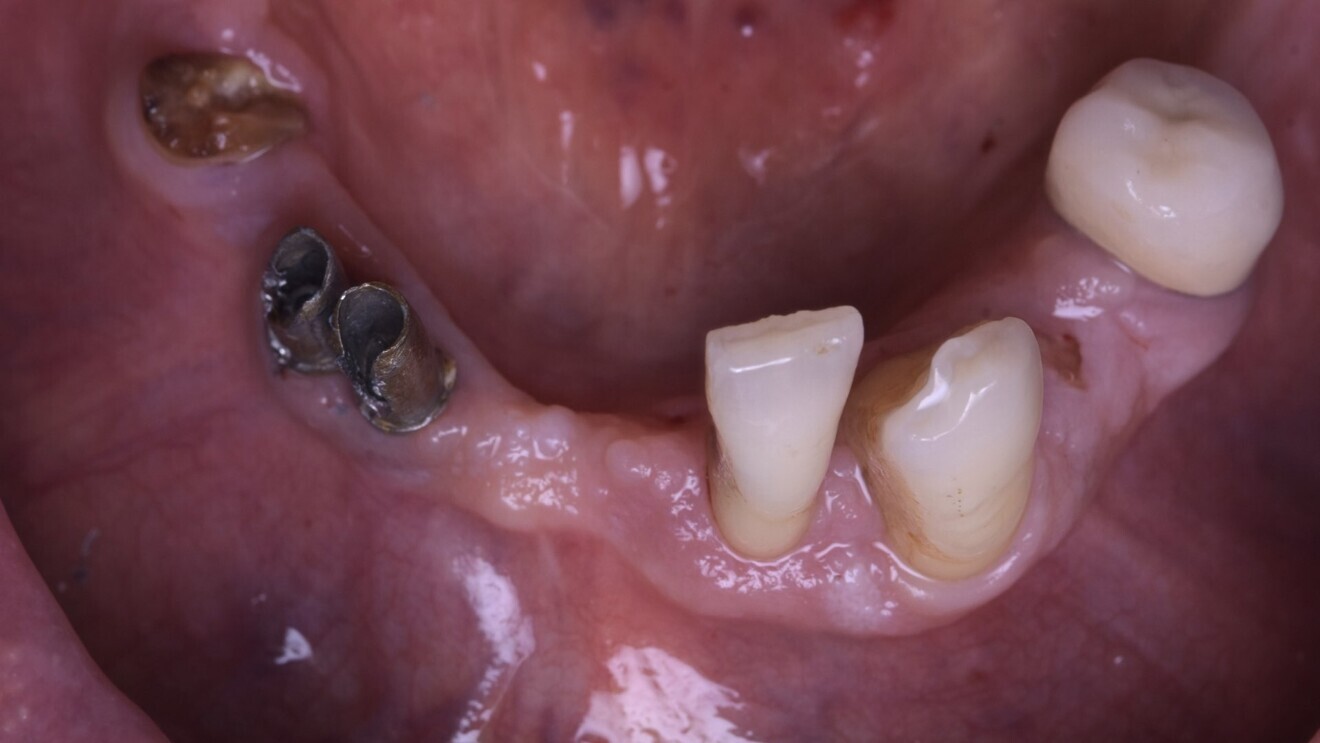

Au niveau mandibulaire (Fig. 14), la cicatrisation mandibulaire de la gencive autour des implants tissue levels est optimale. Nous ne recherchons pas une mise en condition gingivale particulière car à la mandibule la pérennité s’inscrira dans une hygiène adaptée, et donc nous allégeons volontairement l’intrados, afin d’optimiser le passage des brossettes par le patient